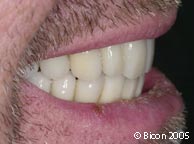

43. |

戴入未抛光的一体化基台冠后病人的微笑。 |